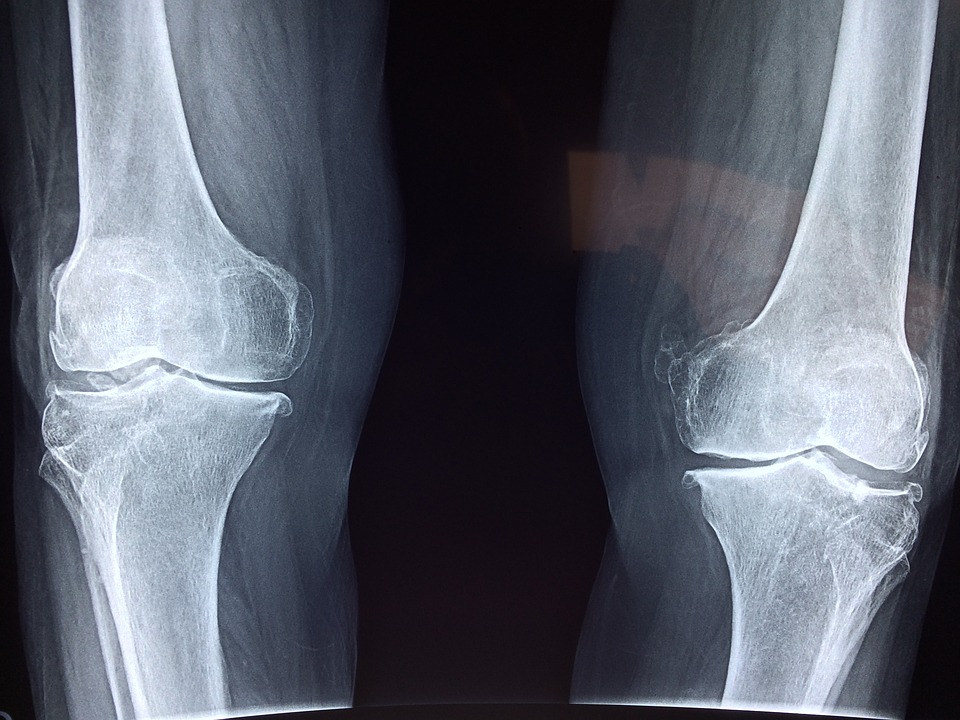

A study comparing the two found that celecoxib improved symptoms more than SAM-e did in a month. However, the second month of the study saw that the two types can be compared. Another supplement for alleviating pain caused by osteoarthritis is chondroitin, which also helps improve cartilage growth.

A study regarding chondroitin found that those who took the supplement revealed that 53 percent of the participants have alleviated knee pains by 20 percent or more.

Boswellia is also known as Indian frankincense and is a resin extract derived from the Boswellia tree. This extract has been used in many herbal medicinal practices for hundreds of years because of its anti-inflammatory properties. A study conducted back in 2003 showed that those who received Boswellia as a treatment for their osteoarthritis had decreased knee pain. Along with less pain, they also found increased knee flexion and were able to walk for longer distances compared to when they did not take the supplement.